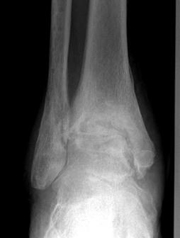

La prótesis se utiliza para sustituir una articulación que no funciona. Las prótesis de cadera y de rodilla son muy utilizadas para tratar la artrosis. La prótesis de tobillo se usa para tratar la degeneración articular de tobillo.

La prótesis de tobillo está indicada cuando la articulación del tobillo no puede seguir realizando su función de movimiento. Cuando pasa esto, las alternativas son fijar la articulación o colocar una prótesis. La ventaja de la prótesis es que se conserva el movimiento. Nuestros especialistas analizarán su caso y le aconsejarán si la prótesis de tobillo es la mejor solución.